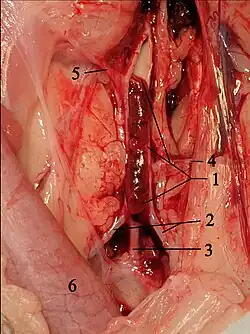

Surgical septal myectomy

Surgical septal myectomy is an open-heart operation done to relieve symptoms in people who remain severely symptomatic despite medical therapy. It has been performed successfully since the early 1960s.[20] Surgical septal myectomy uniformly decreases left ventricular outflow tract obstruction and improves symptoms, and in experienced centers has a surgical mortality of less than 1%, as well as 85% success rate.[40] It involves a median sternotomy (general anesthesia, opening the chest, and cardiopulmonary bypass) and removing a portion of the interventricular septum.[15] Surgical myectomy resection that focuses just on the subaortic septum, to increase the size of the outflow tract to reduce Venturi forces, may be inadequate to abolish systolic anterior motion (SAM) of the anterior leaflet of the mitral valve. With this limited resection, the residual mid-septal bulge still redirects flow posteriorly; SAM persists because flow still gets behind the mitral valve. It is only when the deeper portion of the septal bulge is resected that flow is redirected anteriorly away from the mitral valve, abolishing SAM. With this in mind, a modification of the Morrow myectomy termed extended myectomy, mobilization and partial excision of the papillary muscles has become the excision of choice.[54][55][56][57] In people with particularly large redundant mitral valves, anterior leaflet plication may be added to complete separation of the mitral valve and outflow.[57] Complications of septal myectomy surgery include possible death, arrhythmias, infection, incessant bleeding, septal perforation/defect, and stroke.[40]

Alcohol septal ablation

Alcohol septal ablation, introduced by Ulrich Sigwart in 1994, is a percutaneous technique that involves an injection of alcohol into one or more septal branches of the left anterior descending artery. This is a catheter technique with results similar to the surgical septal myectomy procedure but is less invasive since it does not involve general anesthesia and opening of the chest wall and pericardium (which are done in a septal myectomy). In a select population with symptoms secondary to a high outflow tract gradient, alcohol septal ablation can reduce the symptoms of HCM. In addition, older individuals and those with other medical problems, for whom surgical myectomy would pose an increased procedural risk, would likely benefit from the less-invasive septal ablation procedure.[15][58]